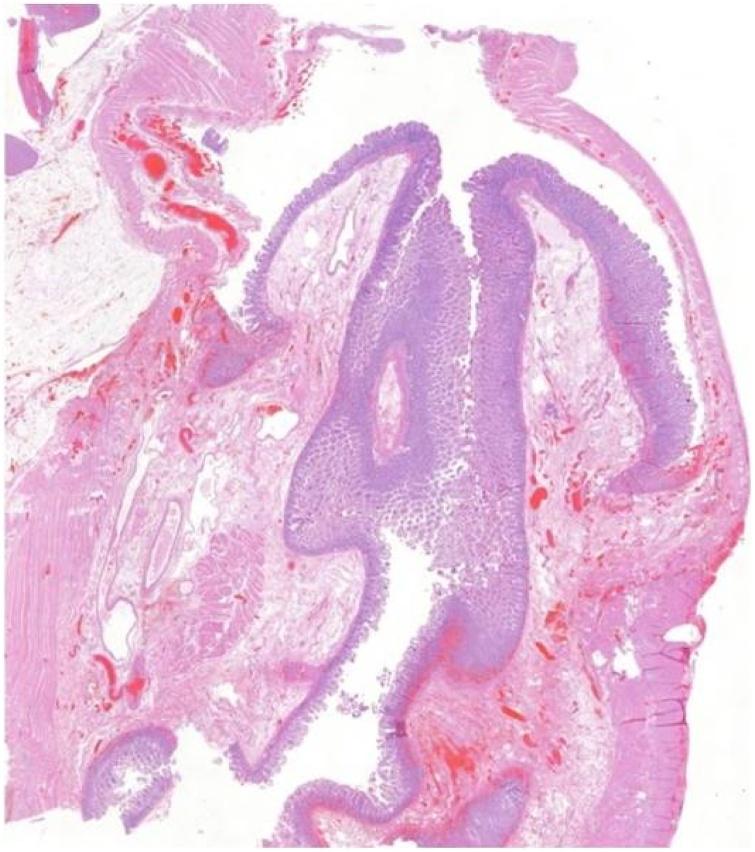

坏死性环状梅克尔憩室致肠梗阻和肠缺血:病例报告及文献复习

Intestinal obstruction and ischemia by necrotic annular Meckel's diverticulum: Case report and review of the literature.

CASE PRESENTATION

A 70-year-old Caucasian male was admitted to the Emergency Department with a two-day history of abdominal pain associated with inability to pass gas or stool, nausea and vomiting. Physical examination revealed abdominal distention and abdominal pain without Blumberg's sign. Abdominal contrast-enhanced computed tomography (CECT) showed small bowel obstruction caused by suspected MD. Laboratory tests reported high serum levels of glycemia, LDH, C-reactive protein and leukocytosis. After diagnosis of intestinal obstruction, the patient underwent exploratory laparotomy: a segmental resection of ischemic distal ileum bearing a necrotic MD was performed. The postoperative course of patient was uneventful.

一名70岁的白种男性因腹痛两天伴无法排气或排便、恶心和呕吐入院急诊科。体格检查发现腹胀和腹痛,无反跳痛。腹部增强计算机断层扫描(CECT)显示疑似MD导致的小肠梗阻。实验室检查报告血糖、乳酸脱氢酶、C反应蛋白血清水平升高及白细胞增多。诊断为肠梗阻后,患者接受了剖腹探查术:对一段带有坏死MD的缺血性回肠末端进行了节段性切除。患者术后恢复顺利。